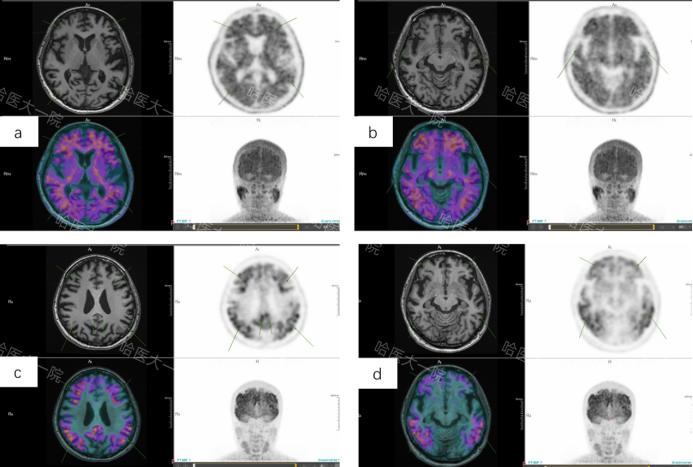

经过核医学科医师图像判读sMRI显示脑萎缩,双侧内嗅皮层、海马及杏仁体萎缩,同机18F-FDG显像双侧颞顶联合区、后扣带回及额叶伴葡糖糖代谢对称性减低,sMRI及18F-FDG显像不符合额颞痴呆典型影像表现;为近一步确诊行18F-AV45及18F-AV1451显像,二者显像均为阳性,综合患者sMRI及多探针联合成像结果为患者明确病因诊断,即认知及情绪障碍致病来源为早发阿尔兹海默症,并协助临床进一步制定治疗用药方案,同时18F-AV1451为患者日后治疗效果评估提供了影像基线。